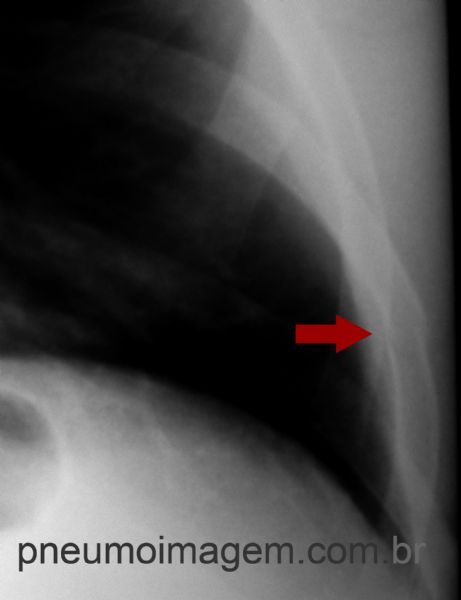

Este paciente asmático de 47 anos apresenta-se com muita dor torácica após crise de tosse. Você consegue identificar nesta radiografia as fraturas de arcos costais presentes como complicação da tosse?

Asthmatic patients 47 years presents with chest pain after coughing. Can you identify in this radiography the fractures of the costal arches present as a complication of cough?

Nesta imagem aproximada pode-se observar a fratura no 9º arco costal à direita. Observe o desalinhamento das corticais ósseas.

Fracture in the 9th rib on the right.